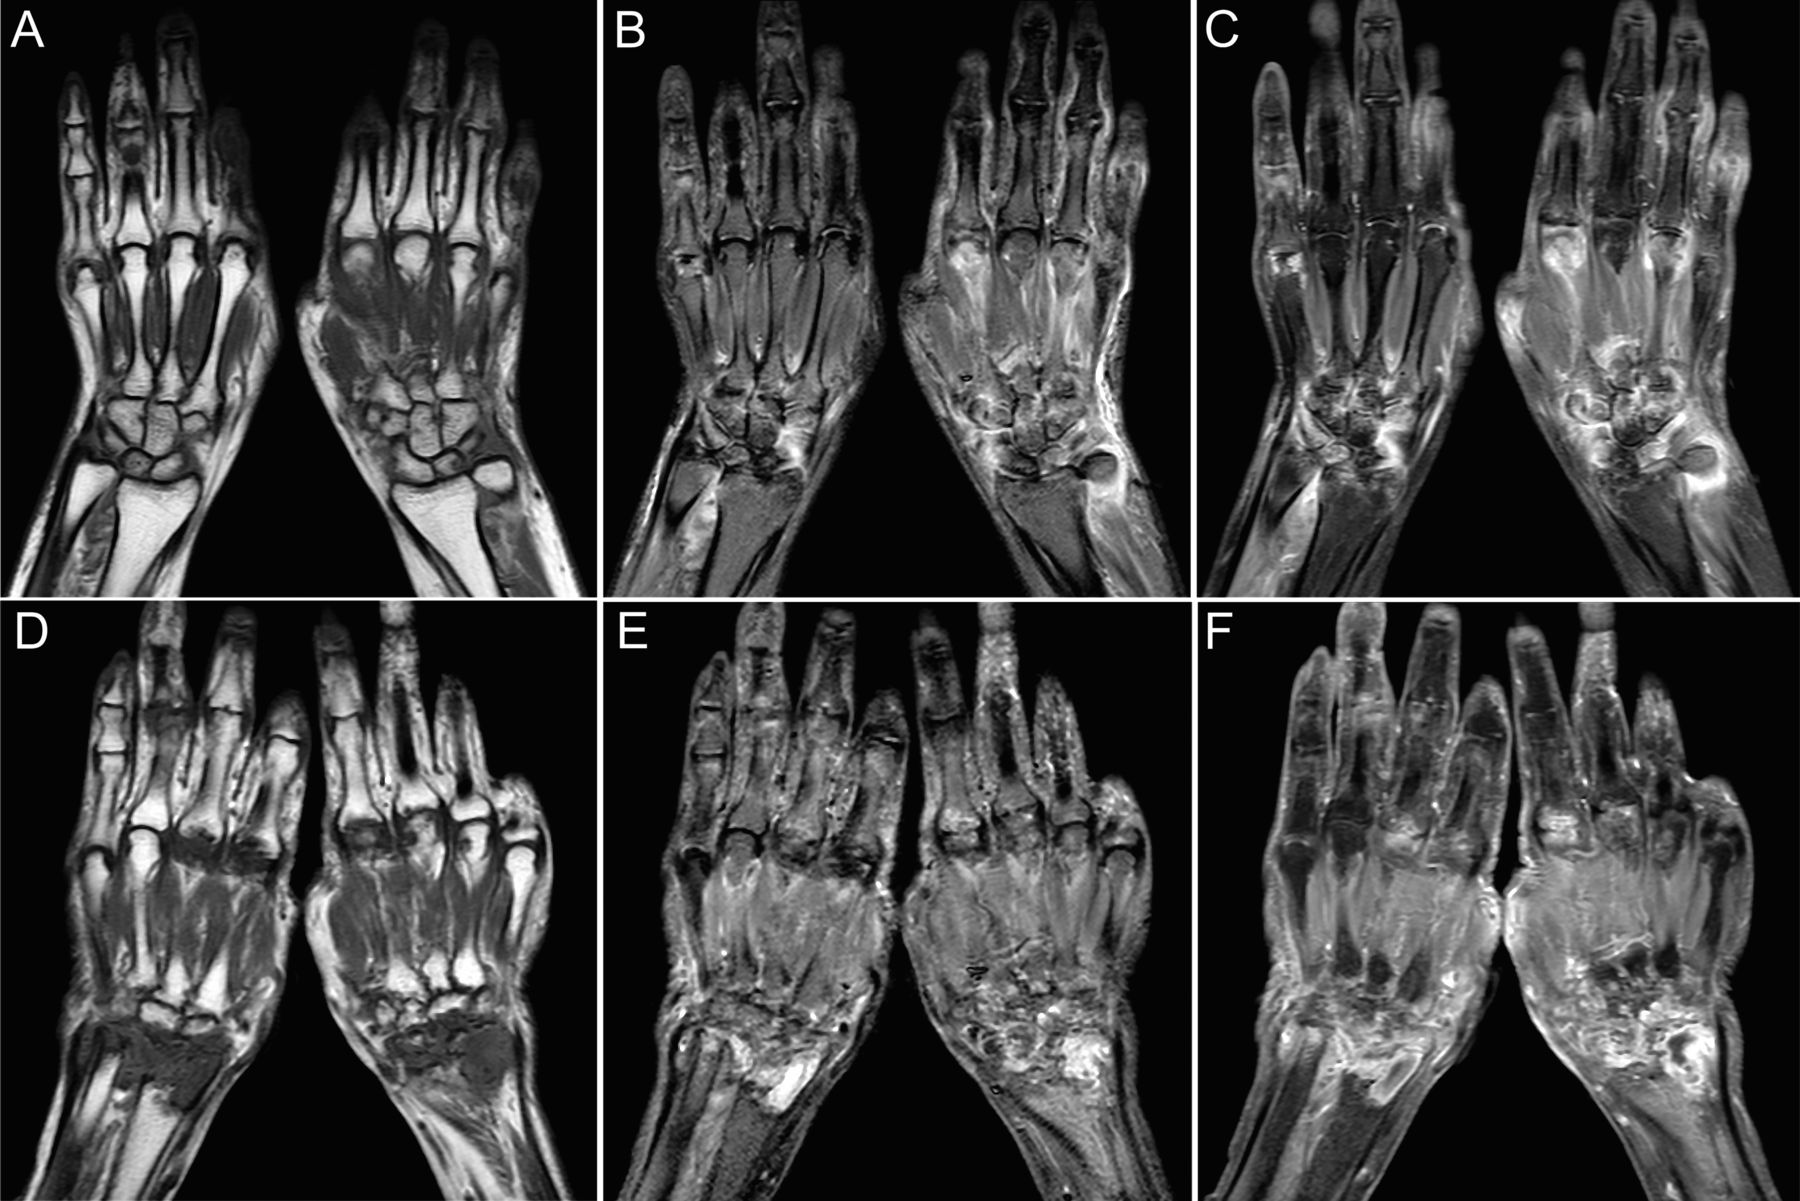

El ve el bileği MR görüntülemesi, eklem kıkırdağının ve yumuşak doku yapılarının üstün görüntü kontrastı yoluyla iyileştirilmiş tanısal sonuçlar sunabilir.

MR tarayıcıları tarafından sağlanan ince yumuşak doku kontrast çözünürlüğü, çeşitli travmatik yaralanmaların, artropatilerin ve neoplastik süreçlerin doğru tanımlanmasına ve değerlendirilmesine olanak tanır.

Eklem kıkırdağının doğrudan görüntülenmesi, kistler ve erozyonlar radyografik olarak belirgin olmadan önce MR ile tespit edilebilir. Sinovit, bursit, osteomiyelit, osteit,

kireçlenme, sedef hastalığı, septik ve romatoid artrit, tümörler, neoplazmalar, yumuşak doku lezyonları ve tümörleri değerlendirilmek için yapılır.